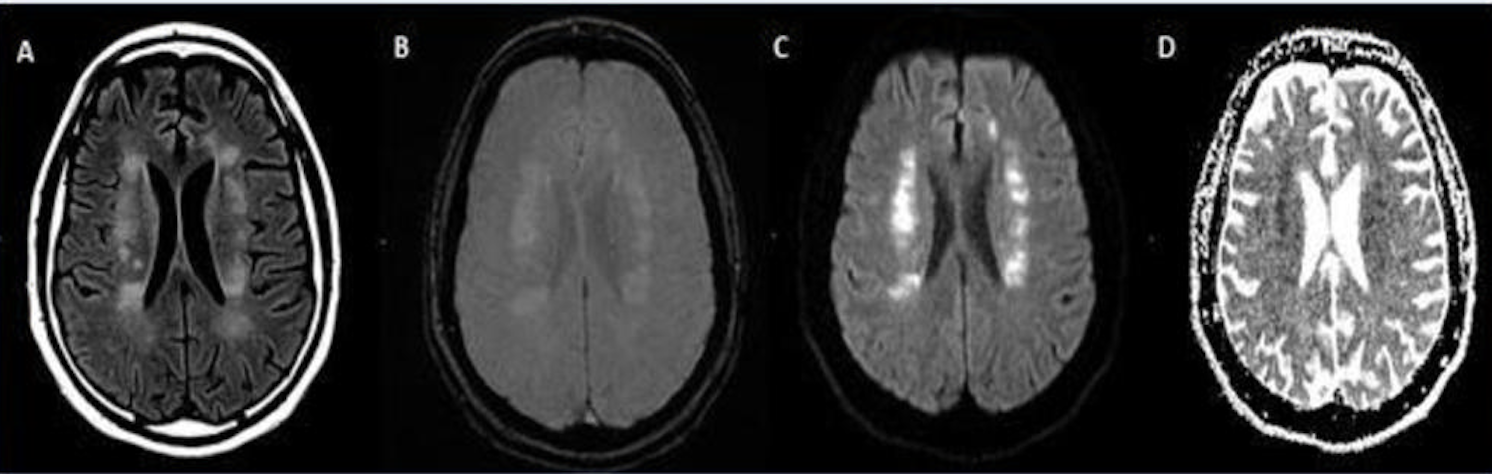

A 62-year-old male with a past medical history of hypertension presenting with seizures. Image courtesy of RSNA

-

A 56-year-old male patient with diabetes and hypertension who presented with complaints of confusion. Courtesy of RSNA